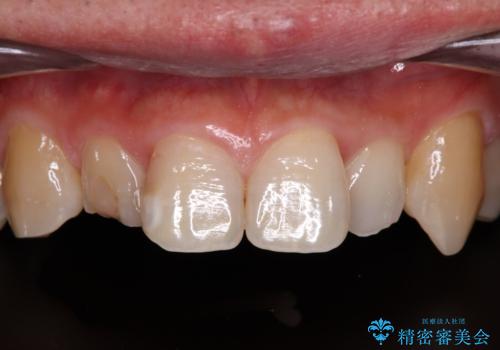

- 内側に倒れている前歯が擦れてしみるとのことで来院された患者様です。

削れていた部分は詰め物が入っていましたが、縁の部分がしみているようで、変色も目立っていたため、オールセラミッククラウンにて補綴治療を行うこととしました。